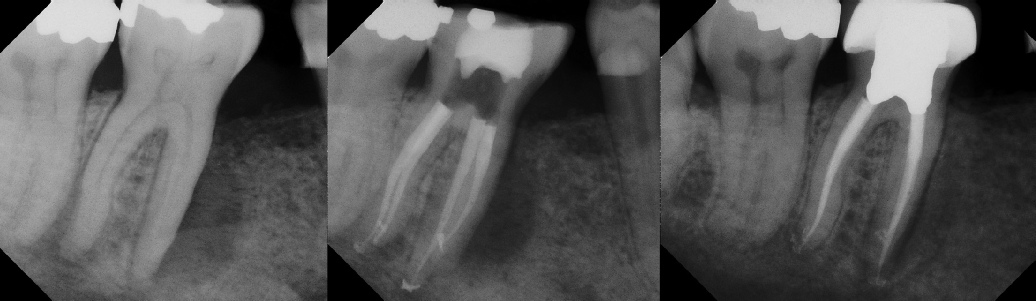

COMPLICATED ANATOMY LARGE LESIONS CALCIFIED CANALS PERFORATION / RESORPTION SEPARATED INSTRUMENTS SURGICAL CASES RETREATMENT / pOST REMOVAL OPEN APICES ACCESS THRU CROWNS Root Canal Case Portfolio

Pre-op Post-op 6 mos.